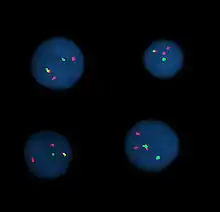

Fluorescent in situ hybridization

Fluorescent in situ hybridization (FISH) refers to using fluorescently labeled probe to hybridize to cytogenetic cell preparations.

The slide is aged using a salt solution usually consisting of 2X SSC (salt, sodium citrate). The slides are then dehydrated in ethanol, and the probe mixture is added. The sample DNA and the probe DNA are then co-denatured using a heated plate and allowed to re-anneal for at least 4 hours. The slides are then washed to remove excess unbound probe, and counterstained with 4',6-Diamidino-2-phenylindole (DAPI) or propidium iodide.

Analysis

Analysis of FISH specimens is done by fluorescence microscopy by a clinical laboratory specialist in cytogenetics. For oncology generally a large number of interphase cells are scored in order to rule out low-level residual disease, generally between 200 and 1,000 cells are counted and scored. For congenital problems usually 20 metaphase cells are scored.